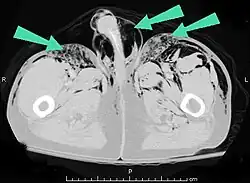

Additionally, it may result from self-injection of air during illicit drug use, particularly in individuals who inject substances intravenously or into unusual sites. There have been documented cases of subcutaneous emphysema occurring in various body regions, including the scrotum, secondary to such self-induced air injection during substance abuse.[23]

Infection

Air can be trapped under the skin in necrotizing infections such as gangrene, occurring as a late sign in gas gangrene,[2] of which it is the hallmark sign. Subcutaneous emphysema is also considered a hallmark of Fournier gangrene.[27] Symptoms of subcutaneous emphysema can result when infectious organisms produce gas by fermentation. When emphysema occurs due to infection, signs that the infection is systemic (i.e. that it has spread beyond the initial location) are also present.[9][21]